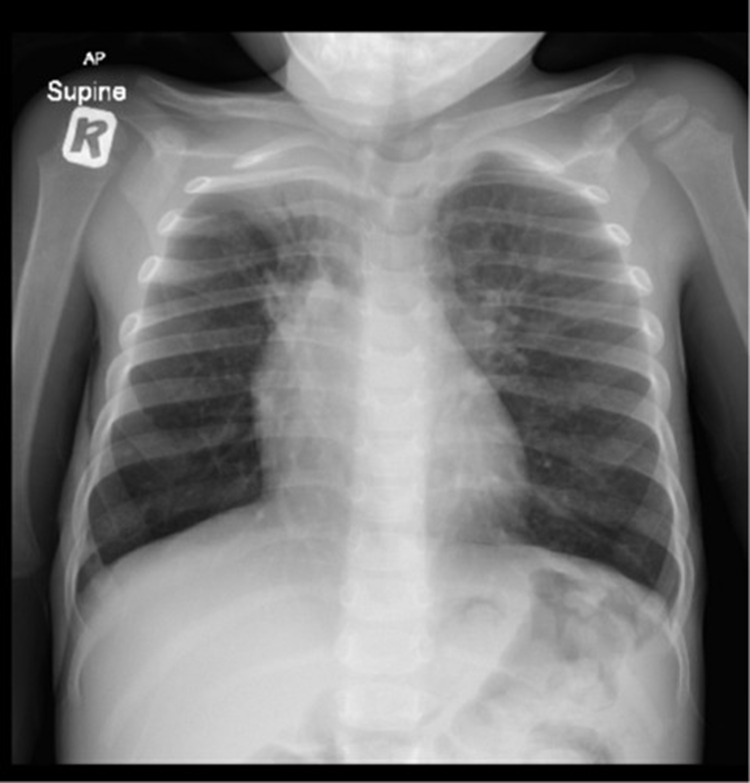

Results: We present the case of a 3-year-old boy with a history of recurrent viral-induced wheezing, initially treated for asthma-like symptoms until he developed persistent hypoxemia. Despite targeted therapy, the patient exhibited persistent respiratory symptoms and consolidative opacities in the right lung. A high-resolution computed tomography (HRCT) scan showed diffuse lung abnormalities, prompting further evaluation. Bronchoscopy with bronchoalveolar lavage revealed Haemophilus influenzae infection, and an open lung biopsy confirmed AFOP. The patient was treated with corticosteroids and azithromycin, leading to significant clinical and radiographic improvement.